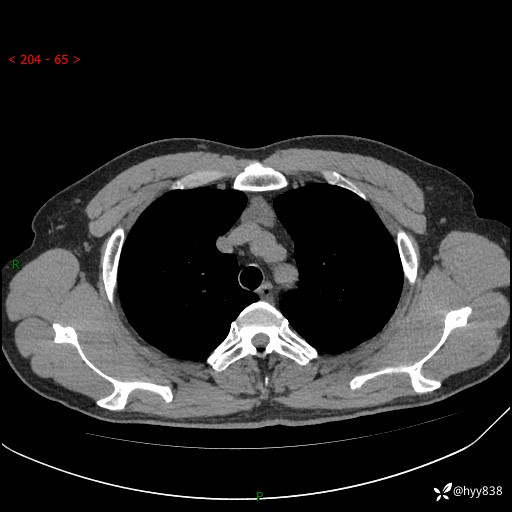

患者性别:女

患者年龄:49岁

简要病史:跟骨骨折,常规CT发现纵隔占位

胸部CT平扫